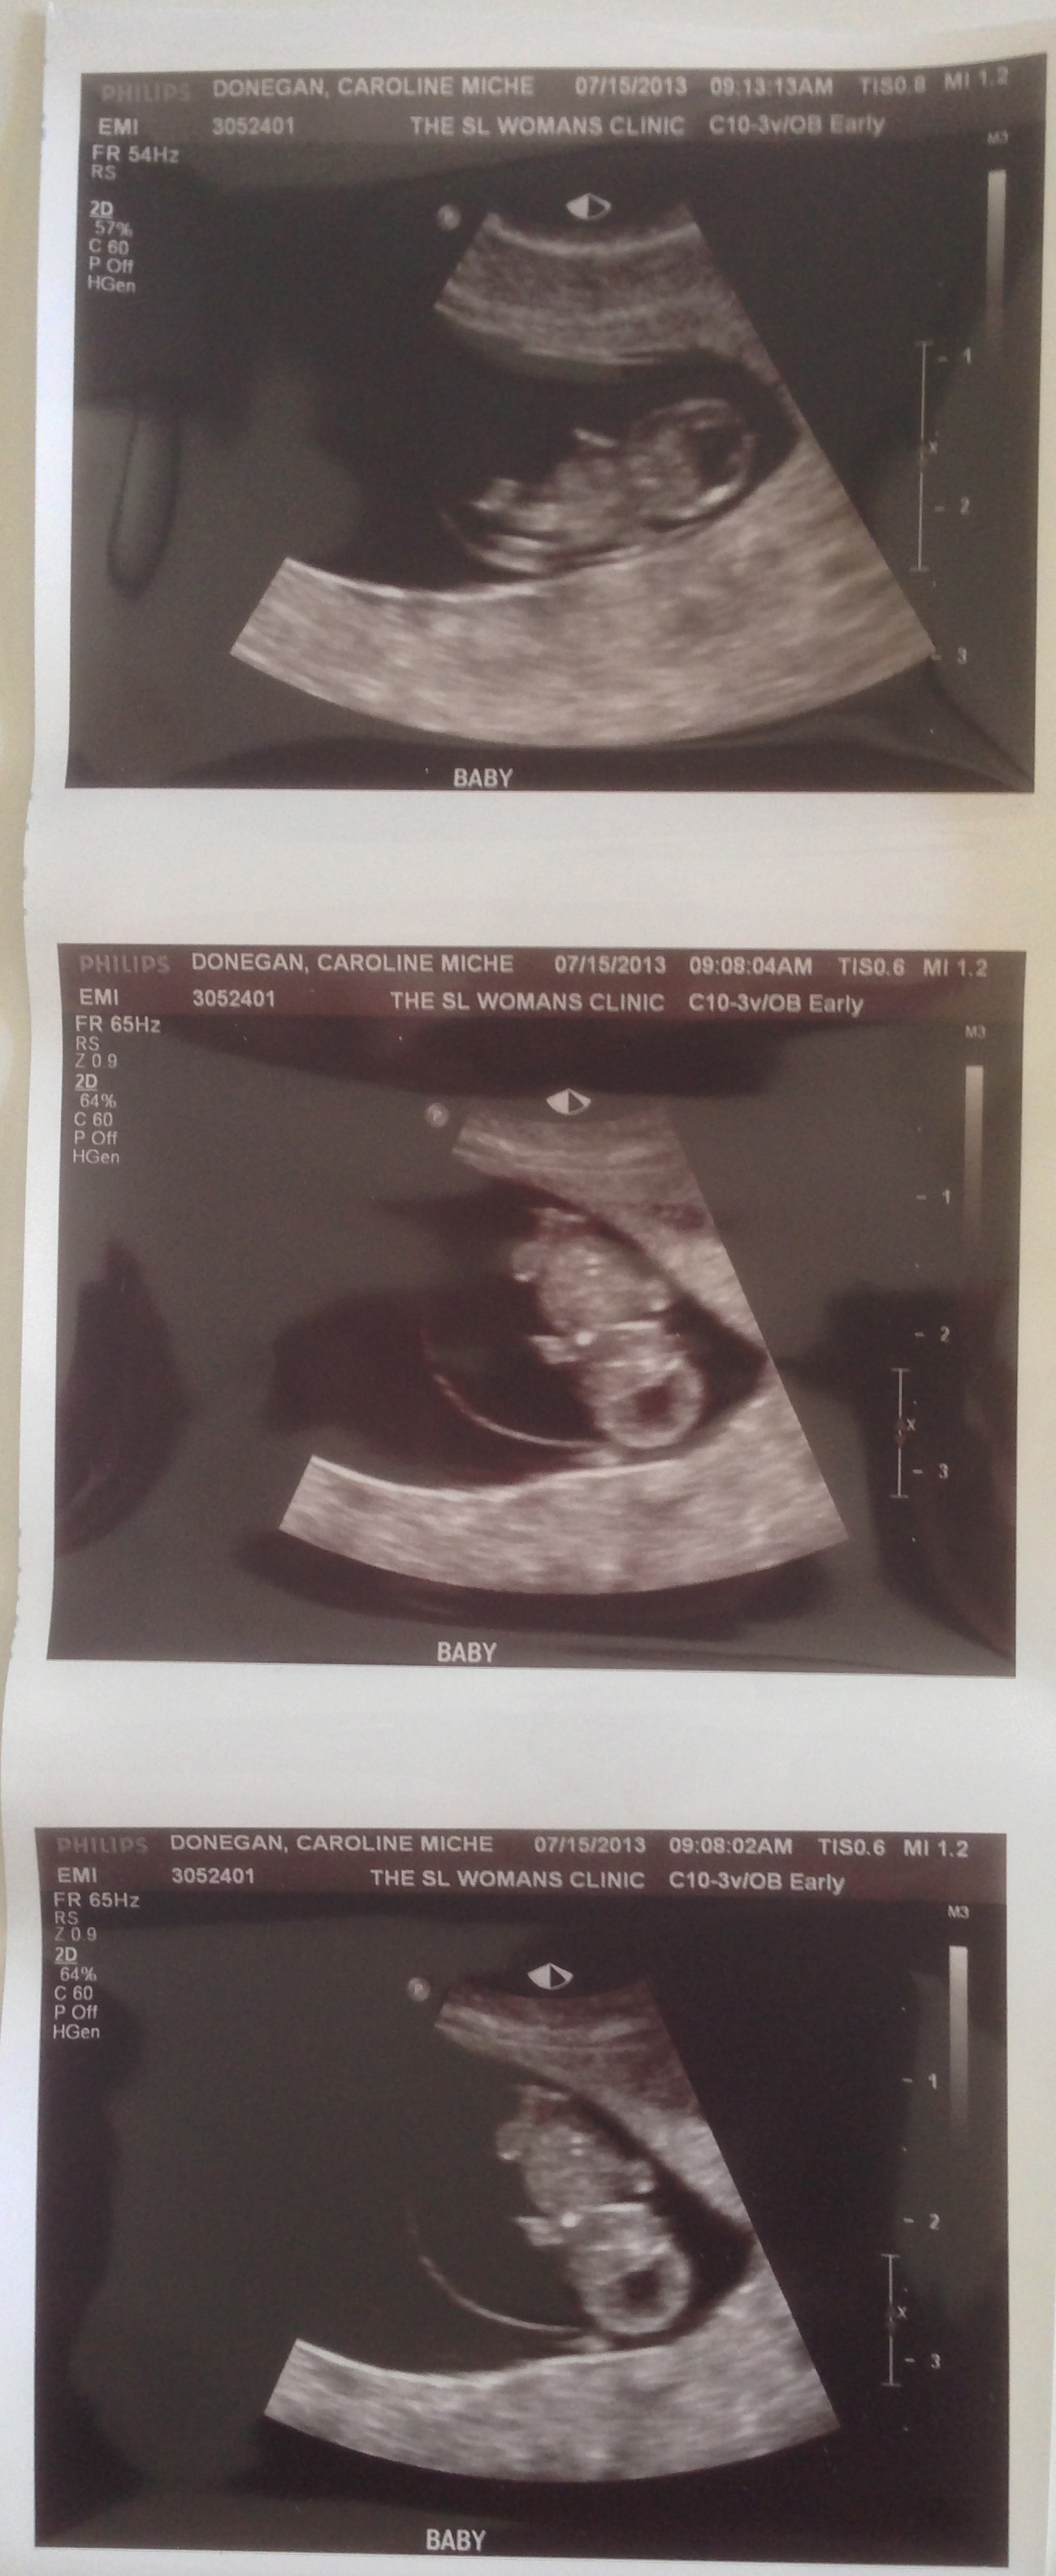

Figured you might want to see your first ultrasound, notice the full rotation that takes place in the 5 minute span:

Well, by incredible I mean you kind of looked like a kidney bean. But while we were watching, you wiggled as if you knew we were looking. You were shaking your hands and feet and even flipped your entire body around. The ultrasound tech said she had never seen any baby do that, so you are obviously special. Right now you are 8 weeks and 4 days along.

At the doctor today they talked about how healthy you and your mom are. just for reference, your mom is insanely healthy. She works out all the time, doesn't drink (not just because you are in there), and is absolutely gorgeous. The doctor today, Dr. Tim West (UA alum btw), said that at this point there is less than a 1% chance of a miscarriage because you are so healthy. Your vitals were all solid, your spine was beginning to be seen and your hands and feet are developing. You are just over 2 centimeters long right now.